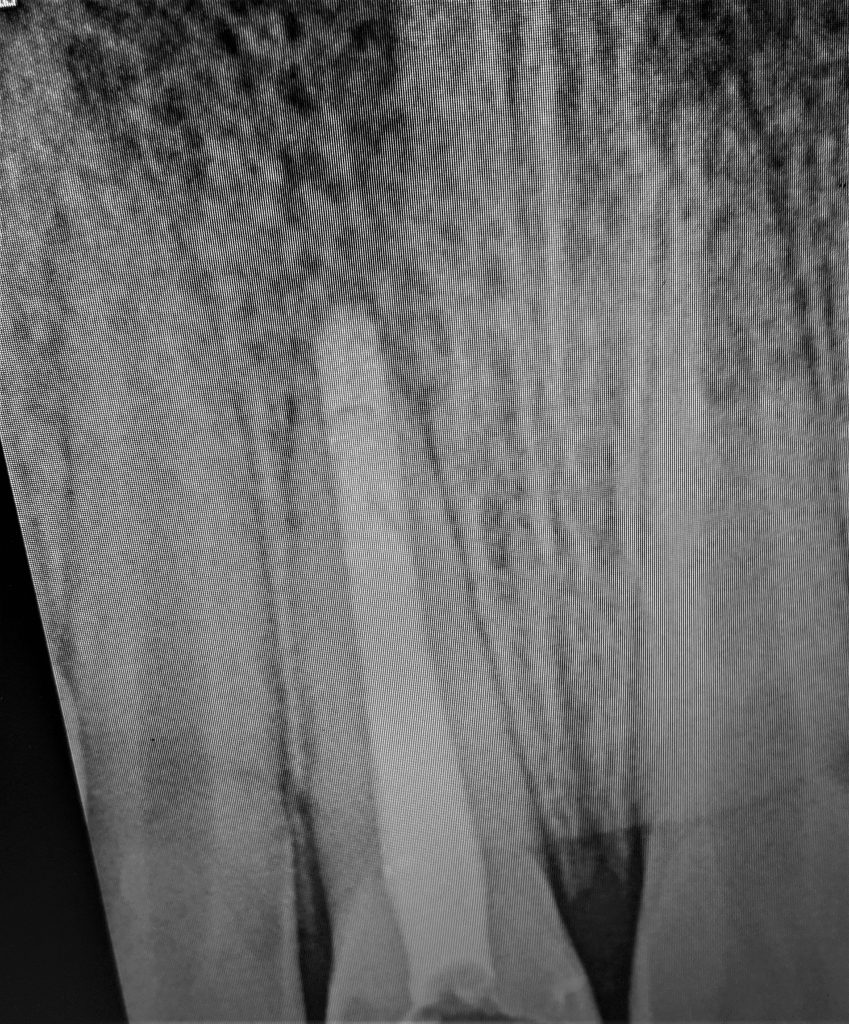

Complete obturation

Internal bleaching by using hydrogen peroxide by WBT

describe by p.mange